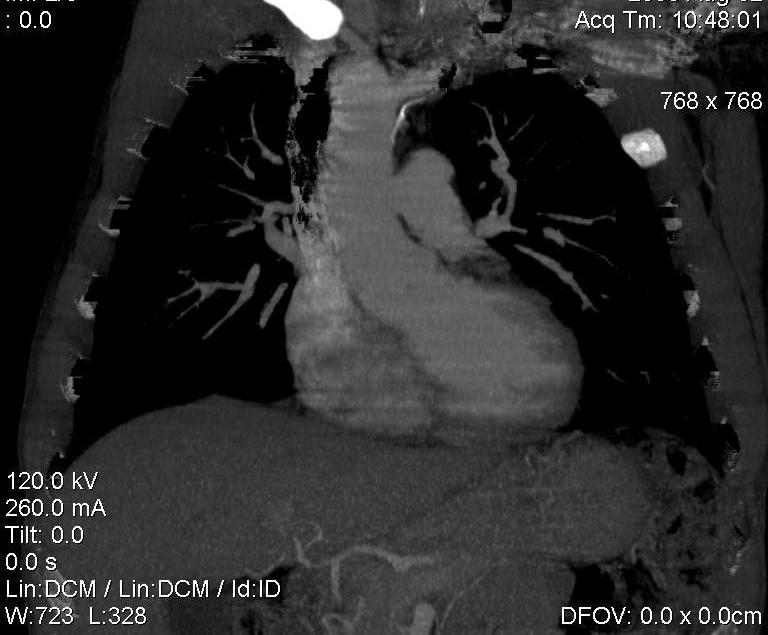

Пациент был направлен на КТ после рентгенографии ОГК, с направительным диагнозом: объёмное образование верхнего средостения.

это аномально расположенная грудная аорта

Конечно, дуга аорты идёт справа от позвоночника (декстра позиция); но есть и ещё одна аномалия той же группы: